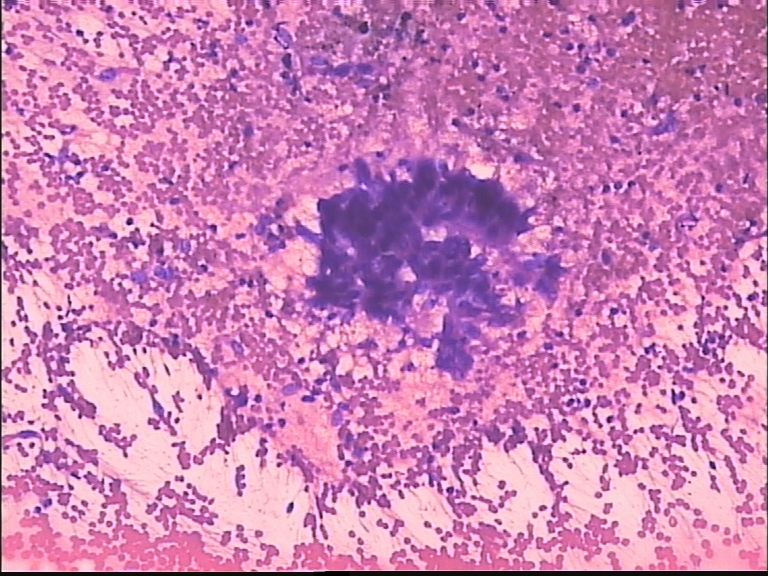

男 70岁,ct肺部见一肿块:结核?肺癌?

未发现明显恶性细胞  好像有多核巨细胞 ?认为 本例要进一步检查除外结核

恶性不能除外

考虑癌。

这个病例有些深染染色质粗异型的核,后边几幅图似乎是退变的多核巨细胞;结核或恶性都不能除外;一般遇到这样的病例我会选择报:见少许深染异型细胞及多核巨细胞;建议穿刺组织活检以进一步排除结核或恶性之可能。

支气管镜活检看到的是粘膜慢性炎伴多核巨细胞反应。

我个人看法是:涂片内未见癌细胞。请注意,一些核略大深染的核都有终板,应该是反应性的支气管粘膜上皮细胞。

未见恶性细胞。